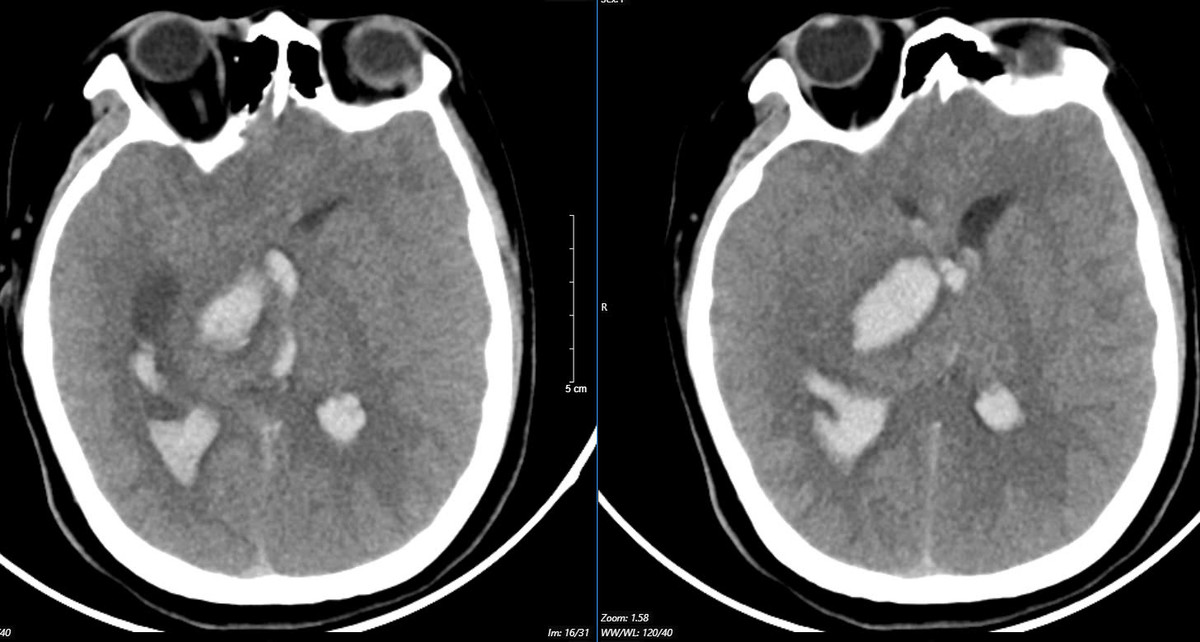

Trường hợp thứ nhất là bệnh nhân 15 tuổi. Sau cơn đau đầu dữ dội, em nhanh chóng rơi vào tình trạng hôn mê.

Bệnh nhân được chuyển đến Trung tâm Đột quỵ, Bệnh viện Bạch Mai trong tình trạng rất nghiêm trọng, thở máy, giãn đồng tử.

| Hình ảnh chụp phim MSCT mạch não chảy máu não đồi thị - não thất do vỡ khối AVM (dị dạng thông động - tĩnh mạch não) bệnh nhân 15 tuổi. Ảnh BVCC |

Kết quả chụp lại phim MSCT mạch não cho thấy tình trạng chảy máu não do vỡ khối dị dạng mạch máu não. Bệnh nhân biến chứng giãn não thất cấp, rối loạn thân nhiệt, sốt cao liên tục 39 - 40 độ C.

Các bác sĩ đã nỗ lực cứu chữa, nhưng tình trạng diễn biến nhanh, bệnh nhân tụt huyết áp, rối loạn thân nhiệt, hôn mê sâu... Sau 2 ngày điều trị, khi được bác sĩ giải thích không còn khả năng cứu chữa, gia đình đưa bệnh nhi về và em đã tử vong sau đó.